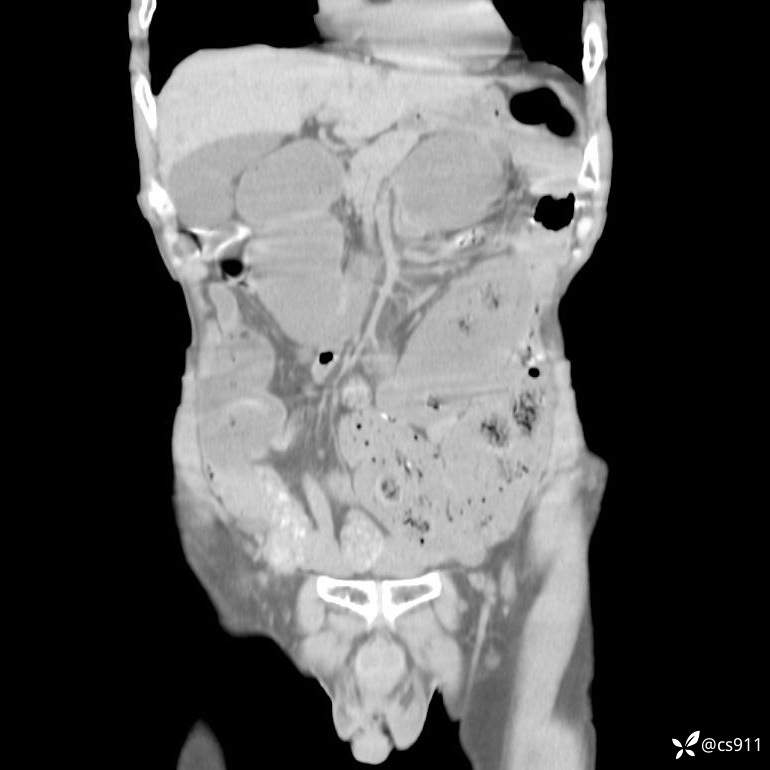

急腹症之急诊CT,原因?答案公布

男,77岁,腹痛、腹胀伴恶心呕吐1天。呕吐胃内容物,非喷射性呕吐,有咖啡色样胃内容物,诉有胃穿孔病史。查体:全腹平,下腹部压痛,全腹无反跳痛,叩诊呈浊音,移动性浊音阴性,肠鸣音减弱,1-2次/分。肛检:直肠未扪及明显肿物,可触及大量粪块。

T 36.6℃ P 80次/分 R 26次/分 BP 100/60mmHg

白细胞(WBC) H 14.55 10e9/L 4-10

中性粒细胞百分率(NEUT%) H 85.7 % 40-75

血淀粉酶(AMY) HH 1859 U/L 35-135

癌胚抗原(CEA) H 27.44 ng/ml 0-5

呕吐物 潜血试验 * 阳性 阴性

患者轮椅入室检查神志清楚, 能配合摆位和呼吸